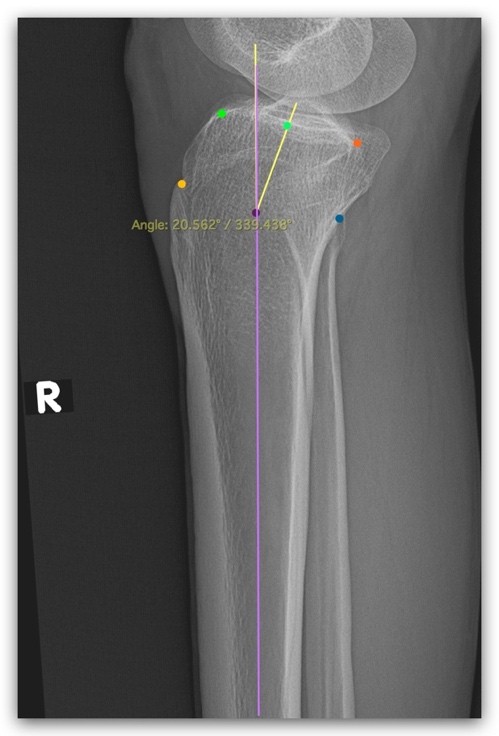

MDA, on a lateral radiograph, a line was drawn through the centers of the outer edges of the tibia at 5 cm and 15 cm below the knee. The MDA was estimated by measuring the angle between the anterior and posterior portions of the metaphysis, a line connecting the center of each surface of the proximal tibia metaphysis (Fig. 2).

Figure 2: Metaphysio-diaphyseal angle measurement.